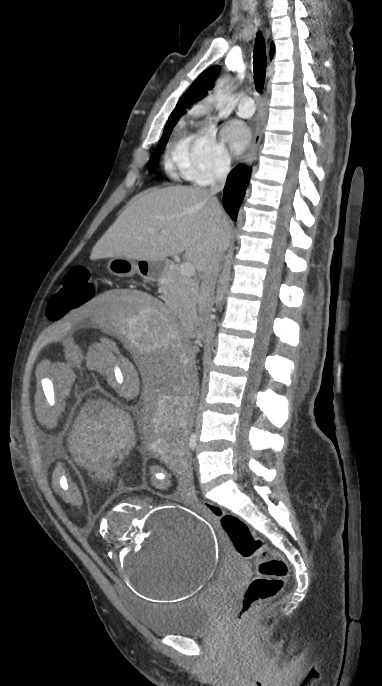

Tomografia komputerowa kobiety w ciąży